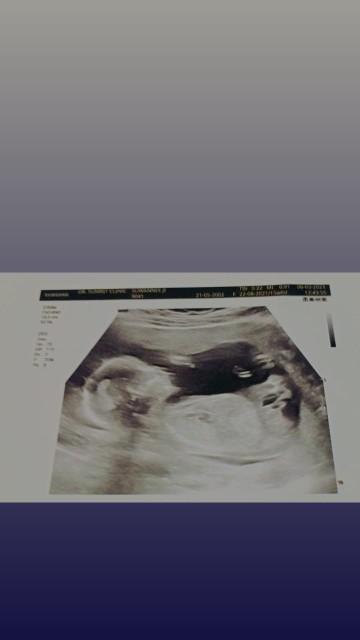

35+3 เด็กหญิง😍